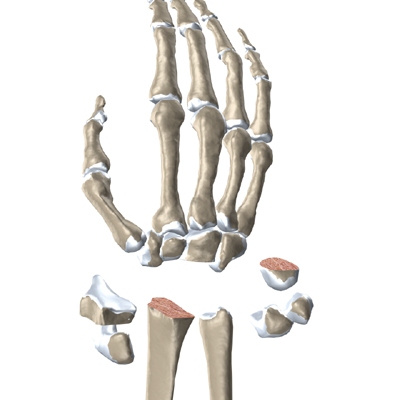

The wrist is made up of eight separate small bones, called the carpal bones. The carpal bones connect the two bones of the forearm, the radius and the ulna, to the bones of the hand. The metacarpal bones are the long bones that lie mostly underneath the palm. The metacarpals are in turn attached to the phalanges (the bones in the fingers and thumb).

One reason that the wrist is so complex is that every small bone forms a joint with the bone next to it. This means many small joints make up the wrist joint. Ligaments connect all the small bones to each other, and to the radius, ulna, and metacarpal bones.

Modern artificial wrist joints are made of metal and plastic. The part that fits against the end of the radius bone of the forearm is called the radial component. It is made up of two pieces. A flat metal piece is placed on the front part of the radius. It has a stem that attaches down into the canal of the bone. A plastic cup fits onto the metal piece, forming a socket for the artificial wrist joint.

The part that replaces the small wrist bones is called the distal component. This piece is made completely of metal. It is globe shaped to fit into the plastic socket on the end of the radius. The metal distal component is attached by two metal stems that fit into the hollow bone marrow cavities of the carpal and metacarpal bones of the hand.

The surgeon needs to make room for the artificial joint. To do this, most of the first row of:

Carpal Bones are Removed

from the wrist. The end of the radius is also shaped to fit the prosthesis.